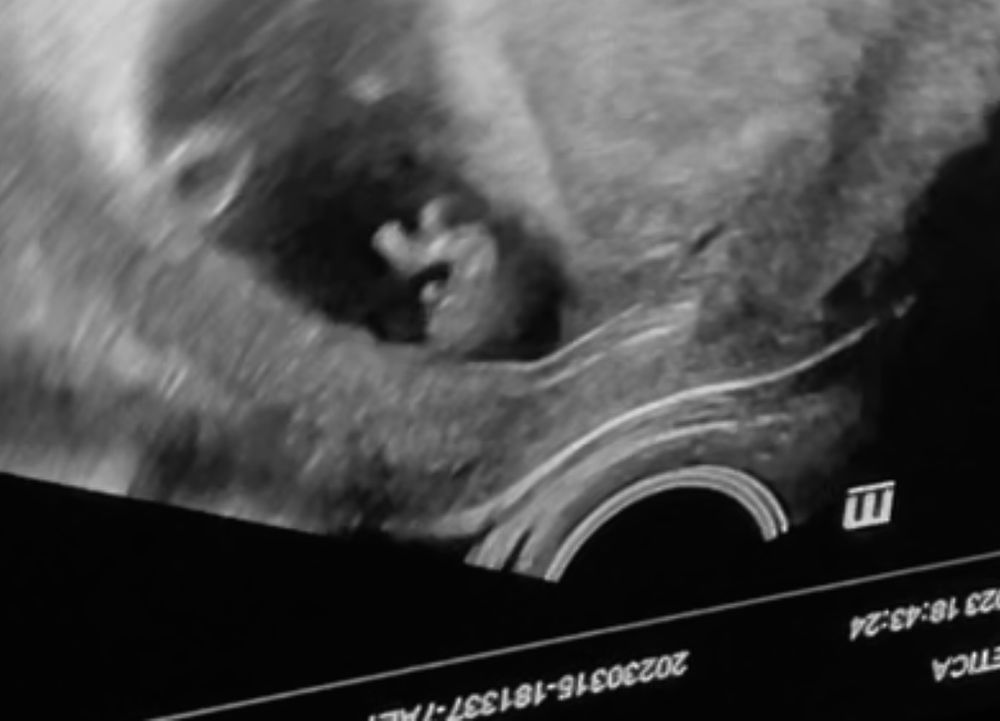

А вот уже скрининг 😂 уже не перепутать😂 лег правильно) Изображение

13.04.2023